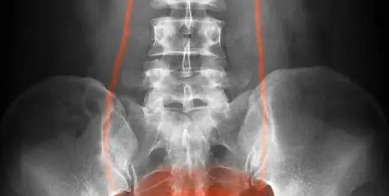

방광염은 세균이 방광에 침투하여 염증을 일으키는 질환으로, 특히 여성에게 빈번하게 발생합니다. 여성은 남성에 비해 요도가 짧고 항문과 요도 사이의 거리가 가까워 외부 세균이 방광으로 침투하기 쉬운 구조적 특성을 가지고 있기 때문입니다. 일반적으로 방광염은 성생활, 체력 저하, 면역력 약화, 잦은 배뇨 억제, 잘못된 위생 습관 등 다양한 원인에 의해 유발되며, 최근에는 비데 사용과 연관된 사례도 늘고 있습니다. 비데는 위생 관리에 도움을 주는 유용한 도구이지만, 잘못된 사용 습관은 오히려 감염의 원인이 될 수 있습니다. 예를 들어, 비데 사용 후 아랫배에 묵직한 통증이 생기거나, 소변을 볼 때 따가움, 타는 듯한 느낌, 잔뇨감이 동반된다면 이는 방광염 초기 증상일 수 있습니다. 특히 수압이 지나치게 강하거나 세정 방향이 뒤에서 앞으로 향하는 경우, 항문 주변의 세균이 요도로 유입되어 방광까지 침투하게 되는 경로가 형성됩니다. 실제로 항문에는 대장균을 비롯한 다양한 균이 존재하는데, 이들이 비데 물살에 의해 이동하게 되면 방광염의 위험이 크게 증가할 수 있습니다. 공공시설에 설치된 비데는 더욱 주의가 필요합니다. 여러 사람이 사용하는 공용 비데의 경우, 노즐이나 버튼이 충분히 소독되지 않으면 오염이 누적되고, 그로 인해 교차 감염이 발생할 수 있습니다. 가정용 비데라고 해서 안전하다는 보장도 없습니다. 비데의 수압이 너무 강하거나 물 온도가 높을 경우, 민감한 피부에 자극을 주어 점막 손상 및 면역 저하 상태에서 세균 감염이 더 쉽게 일어날 수 있습니다. 또한, 장시간 비데를 사용하거나 하루에 여러 번 반복적으로 사용하는 것도 질 내 유익균 균형을 무너뜨릴 수 있어 감염 가능성을 높이는 요인이 됩니다.

방광염의 주요 증상은 빈뇨, 배뇨통, 잔뇨감, 배뇨 시 작열감이며, 이와 함께 하복부의 묵직한 통증이나 압박감이 나타나기도 합니다. 일부 환자는 소변에서 냄새가 강해지거나 탁한 색을 띠는 등의 변화를 느끼기도 하며, 증상이 심할 경우 피가 섞인 소변이 나오는 경우도 있습니다. 이런 상태에서 치료를 미루면 염증이 상부 요로로 번져 신장까지 영향을 줄 수 있는데, 이를 ‘신우신염’이라고 하며 고열과 옆구리 통증을 동반해 훨씬 더 위험한 상황으로 발전할 수 있습니다. 따라서 평소보다 배뇨 횟수가 잦아졌거나, 화장실에 다녀온 뒤에도 시원하지 않고 잔여감이 계속된다면 방광염을 의심하고 병원을 방문해 소변 검사와 배뇨 습관 체크를 받는 것이 중요합니다. 방광염은 조기에 진단받고 항생제 치료를 시작하면 수일 내에 호전되지만, 이를 방치하거나 자주 재발하게 되면 만성화되어 삶의 질을 크게 저하시키는 질환으로 이어질 수 있습니다. 특히 비데를 사용할 때는 수압을 약하게 하고, 세정 방향을 앞에서 뒤로 유지하며, 사용 후에는 반드시 충분히 건조시키는 습관을 들이는 것이 감염 예방에 도움이 됩니다.

요도염은 요도에 염증이 생기는 질환으로, 단순히 성병에 의해서만 발생하는 것은 아닙니다. 위생 상태가 불량하거나, 비위생적인 환경에서 생활할 경우에도 충분히 발생할 수 있으며, 특히 비데 사용, 과도한 세정, 피부 마찰, 알레르기 반응, 스트레스 등 다양한 일상적 요인들도 요도염을 유발할 수 있습니다. 일반적으로 요도염은 남성보다 여성에게 더 흔하게 나타나는데, 이는 여성의 요도가 남성보다 짧고, 항문과 가까워 세균이 침투하기 쉬운 구조이기 때문입니다. 최근에는 비데 사용 습관이 요도염과 연관되어 나타나는 사례가 증가하고 있습니다. 비데는 개인 위생을 위해 널리 사용되고 있지만, 올바르지 않은 사용법은 오히려 감염 위험을 높일 수 있습니다. 특히 비데 사용 직후부터 요도 부위에 따끔거림이나 화끈거림이 느껴진다면, 이는 요도염의 초기 증상일 수 있습니다. 수압이 너무 강하거나 물 온도가 지나치게 높을 경우, 민감한 요도 점막에 자극을 가하게 되고, 이로 인해 자연스러운 방어막이 손상되어 세균이 침투할 수 있는 환경이 만들어집니다.

또한, 비데 사용 후 물기를 제대로 제거하지 않고 속옷을 착용하는 습관 역시 문제가 됩니다. 습한 환경은 세균이 증식하기 가장 좋은 조건이며, 특히 요도 주변이 지속적으로 축축한 상태로 유지되면 세균 번식과 감염 가능성이 더욱 커집니다. 따라서 비데 사용 후에는 마른 수건이나 휴지로 물기를 잘 닦아내야 하며, 가능하다면 비데의 건조 기능을 활용하거나 드라이기 바람으로 부드럽게 건조하는 것도 도움이 됩니다. 요도염의 주요 증상은 소변 시 따가움, 잔뇨감, 요도 부위의 가려움 혹은 화끈거림, 투명하거나 노란 분비물 배출 등입니다. 초기에는 단순한 불편함 정도로 느껴질 수 있지만, 치료 없이 방치할 경우 만성 요도염으로 발전하거나, 방광염, 신우신염, 심한 경우에는 신장까지 염증이 퍼질 수 있는 위험이 있습니다. 여성의 경우 질염과 동반되거나 감별이 어려울 수 있으므로, 자가 판단보다는 의료기관에서 정확한 진단을 받는 것이 필요합니다.